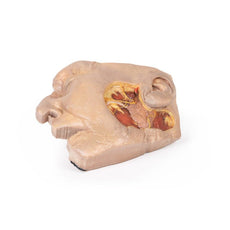

The deep level of dissection has exposed parts of the infratemporal fossa

(through partial removal of the mandibular ramus and corpus) and dissection

of retromandibular tissues. At the inferior margin of the dissection window,

the cut edge of the retromandibular vein lies adjacent to the submandibular

gland and the ascending path of the facial artery as it cross towards to angle

of the mouth. Just superior to the cut retromandibular vein is the posterior

belly of the digastric muscle, overlying a small exposure of the deeper

internal jugular vein.

Just posterior to the retained ascending ramus of the mandible are the

external carotid artery and the occipital artery (running in parallel prior

to passing posteriorly). Tracing the external carotid artery superiorly, the

posterior auricular artery, superficial temporal artery, and maxillary artery are

all visible. The maxillary artery passes deep to the lateral pterygoid muscle

and into the infratemporal fossa, reappearing superior to the lateral pterygoid

as it passes into the pterygomaxillary fissure. Along its course, it gives rise

to the posterior deep temporal artery, the inferior alveolar artery (which is

exposed in the dissected mandibular corpus), the anterior deep temporal

artery, and the posterior superior alveolar artery. Finally, the inferior alveolar

nerve can be seen coursing within the opened mandibular corpus, and the

lingual nerve resting on the medial pterygoid. The buccinator muscle is also

retained, with the distal part of the parotid duct preserved as it enters the

muscle towards the oral mucosa